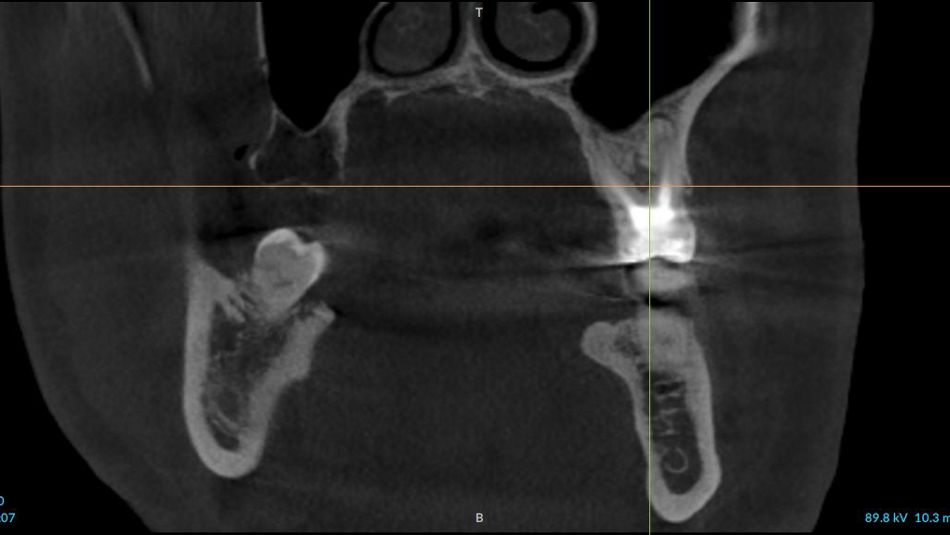

3a. 3b. 3c. 3D volumetric diagnosis and planning of implant therapy.

3a

3b

3c

10a. 10b. 10c. 3D scans and radiograph control of the implantplacement.

10a

10b

10c